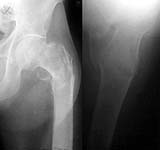

A male, 77 years old, admitted to us after a fall with the fracture (see attached). Features of the case - the patient is a pulmonary surgeon, professor and a former head of the largest pulmonary center here, still works as a scientific consultant. Hb - 77 g/l, Hct - 22%, and he doesn't allow any blood transfusion neither now nor later (). He is mentally alert but quickly gets tired. He is not obese. Very active smoker - 3 packs daily.

On these films, it looks like a comminuted fracture that involves the whole trochanteric region - greater and lesser trochs busted, and maybe even some extension below the lesser trochanter, into the subtroch region.